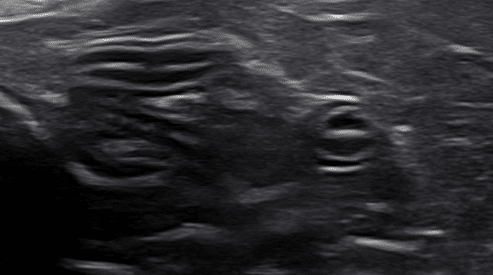

Occasionally, inflammatory bowel disease, specifically protein-losing enteropathy in dogs, can present on ultrasound as linear hyperechoic striations within the mucosal layer (Figure 3). These hyperechoic striations have been determined to be dilated lacteals associated with lymphangiectasia. One complicating factor is that the lacteals will dilate normally after a recent meal ingestion; thus, one of many reasons fasting before ultrasound is required. With protein-losing enteropathy, abdominal effusion may also be present secondary to hypoproteinemia.

Figure 3 (above): Example of hyperechoic striations within the mucosal layer due to dilated lacteals in the small intestinal wall as seen with lymphangiectasia.